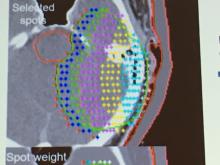

Radiation therapy has become increasingly effective and safe as vendors continue to innovate technologies that benefit the patient. At ASTRO 2018, this patient-centric approach was exemplified and demonstrated not only in ways that match treatments to patients, but in how technologies can adjust to patient movement and anatomical changes, and to increase the precision of treatments. ITN Contributing Editor Greg Freiherr showcases several new technologies that are helping to advance this field.

Proton Therapy | October 10, 2023

Tune in to ITN’s latest “One on One” video series with Michael Butkus, PhD, for insights into proton therapy advancements. Butkus is the co-medical director and head of proton physics at the Dwoskin Proton Center at the Sylvester Comprehensive Cancer Center, part of the University of Miami/UHealth Medical System. A board member of the National Association of Proton Therapy (NAPT), Butkus spoke with ITN’s managing editor to discuss how physicists, physicians and vendors are collaborating to expand availability of proton therapy and improve the health of patients being treated.